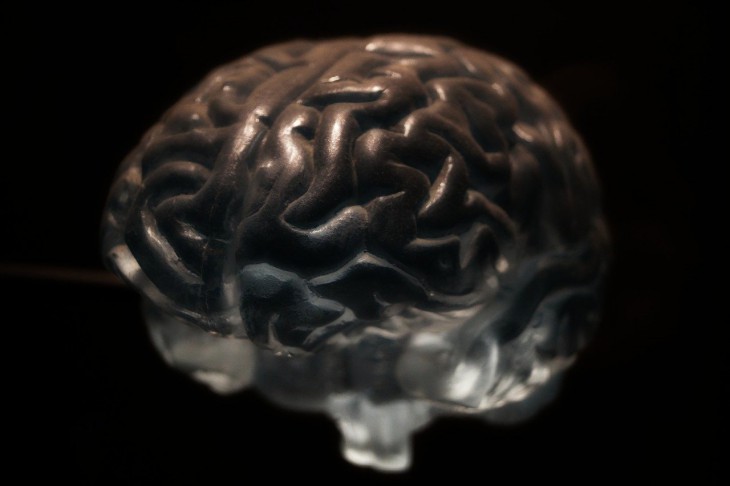

Исследователям из Орегонского института здравоохранения и науки Соединенных Штатов удалось установить, что подобная группа нервных клеток есть и у человека. Как правило, они отвечают за развитие мелкой моторики и находятся в коре головного мозга.

Чтобы прийти к подобным выводам, изучался этот орган зебрового вьюрка. Оказалось, что некоторые нейроны способны трансформировать в код белки ионных каналов натрия. Именно они отвечают за электрические сигналы, производящиеся между клетками нервной системы.